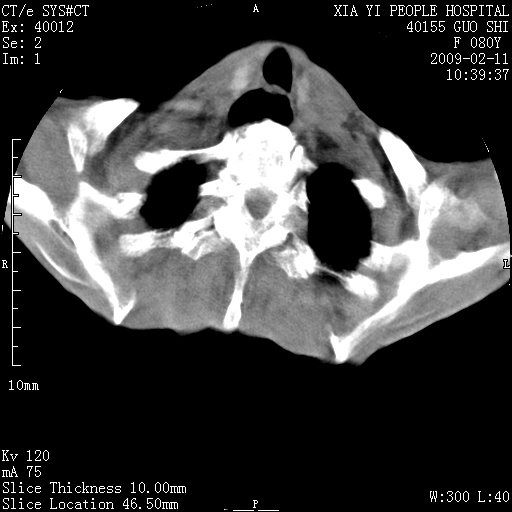

以下是引用随光逐影在2009-2-16 16:34:00的发言:[br]1)考虑右前纵隔皮样囊肿。2)双侧少量胸腔积液。

以下是引用zjzjr在2009-2-16 17:30:00的发言:[br]支持囊性畸胎瘤 双侧少量胸腔积液。